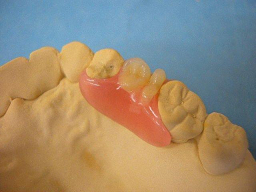

ホワイトコートは、以下のような色調で、自然ではありませんが、多くの方に喜んでもらっていました。これまでは他に方法がなかったので、やむおえません。

このホワイトコートは、3ヶ月くらいで部分的にはがれてきますが、運がよければ1年以上はがれずに維持できています。歯は全く削りません。

見た目は、やはり グラディアダイレクトには及びません。

今回のグラディアダイレクトは、歯の表面の処理方法や接着方法がホワイトコートよりも優れているので、数年は問題なく維持できると思っています。

おそらくこれからは、見た目の自然さから、ホワイトコートを選ぶ患者さんは減り、グラディアダイレクトに変わっていくと思います。